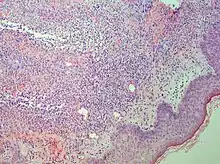

Interface dermatitis with lichenoid inflammation

Main conditions[2]CharacteristicsMicrographPhotograph

Generally/Not otherwise specified Typical findings:[2]

• In the papillary dermis: a confluent, band-like, dense inflammation of mainly small lymphocytes and a few histiocytes, along or hugging the dermoepidermal junction.

• Often vacuolar degeneration of basal keratinocytes and apoptotic bodies (colloid or Civatte bodies).